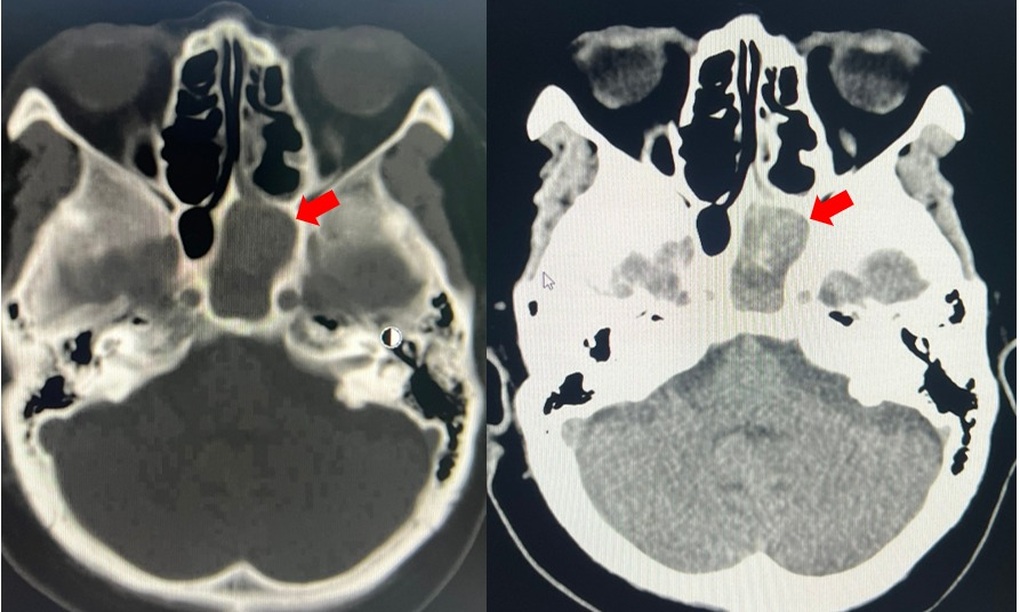

Tomografia computerizată și rezultatele paraclinice ulterioare au stabilit, de asemenea, că pacienta avea sinuzită sfenoidă stângă cauzată de o ciupercă, cu o infecție. În plus, s-a observat că avea și numeroase afecțiuni preexistente, cum ar fi hipertensiune arterială, boală renală cronică în stadiul III și diabet zaharat de tip 2.

Imagine a masei sinusului sfenoidal stâng (săgeată roșie) (Foto: Spital).